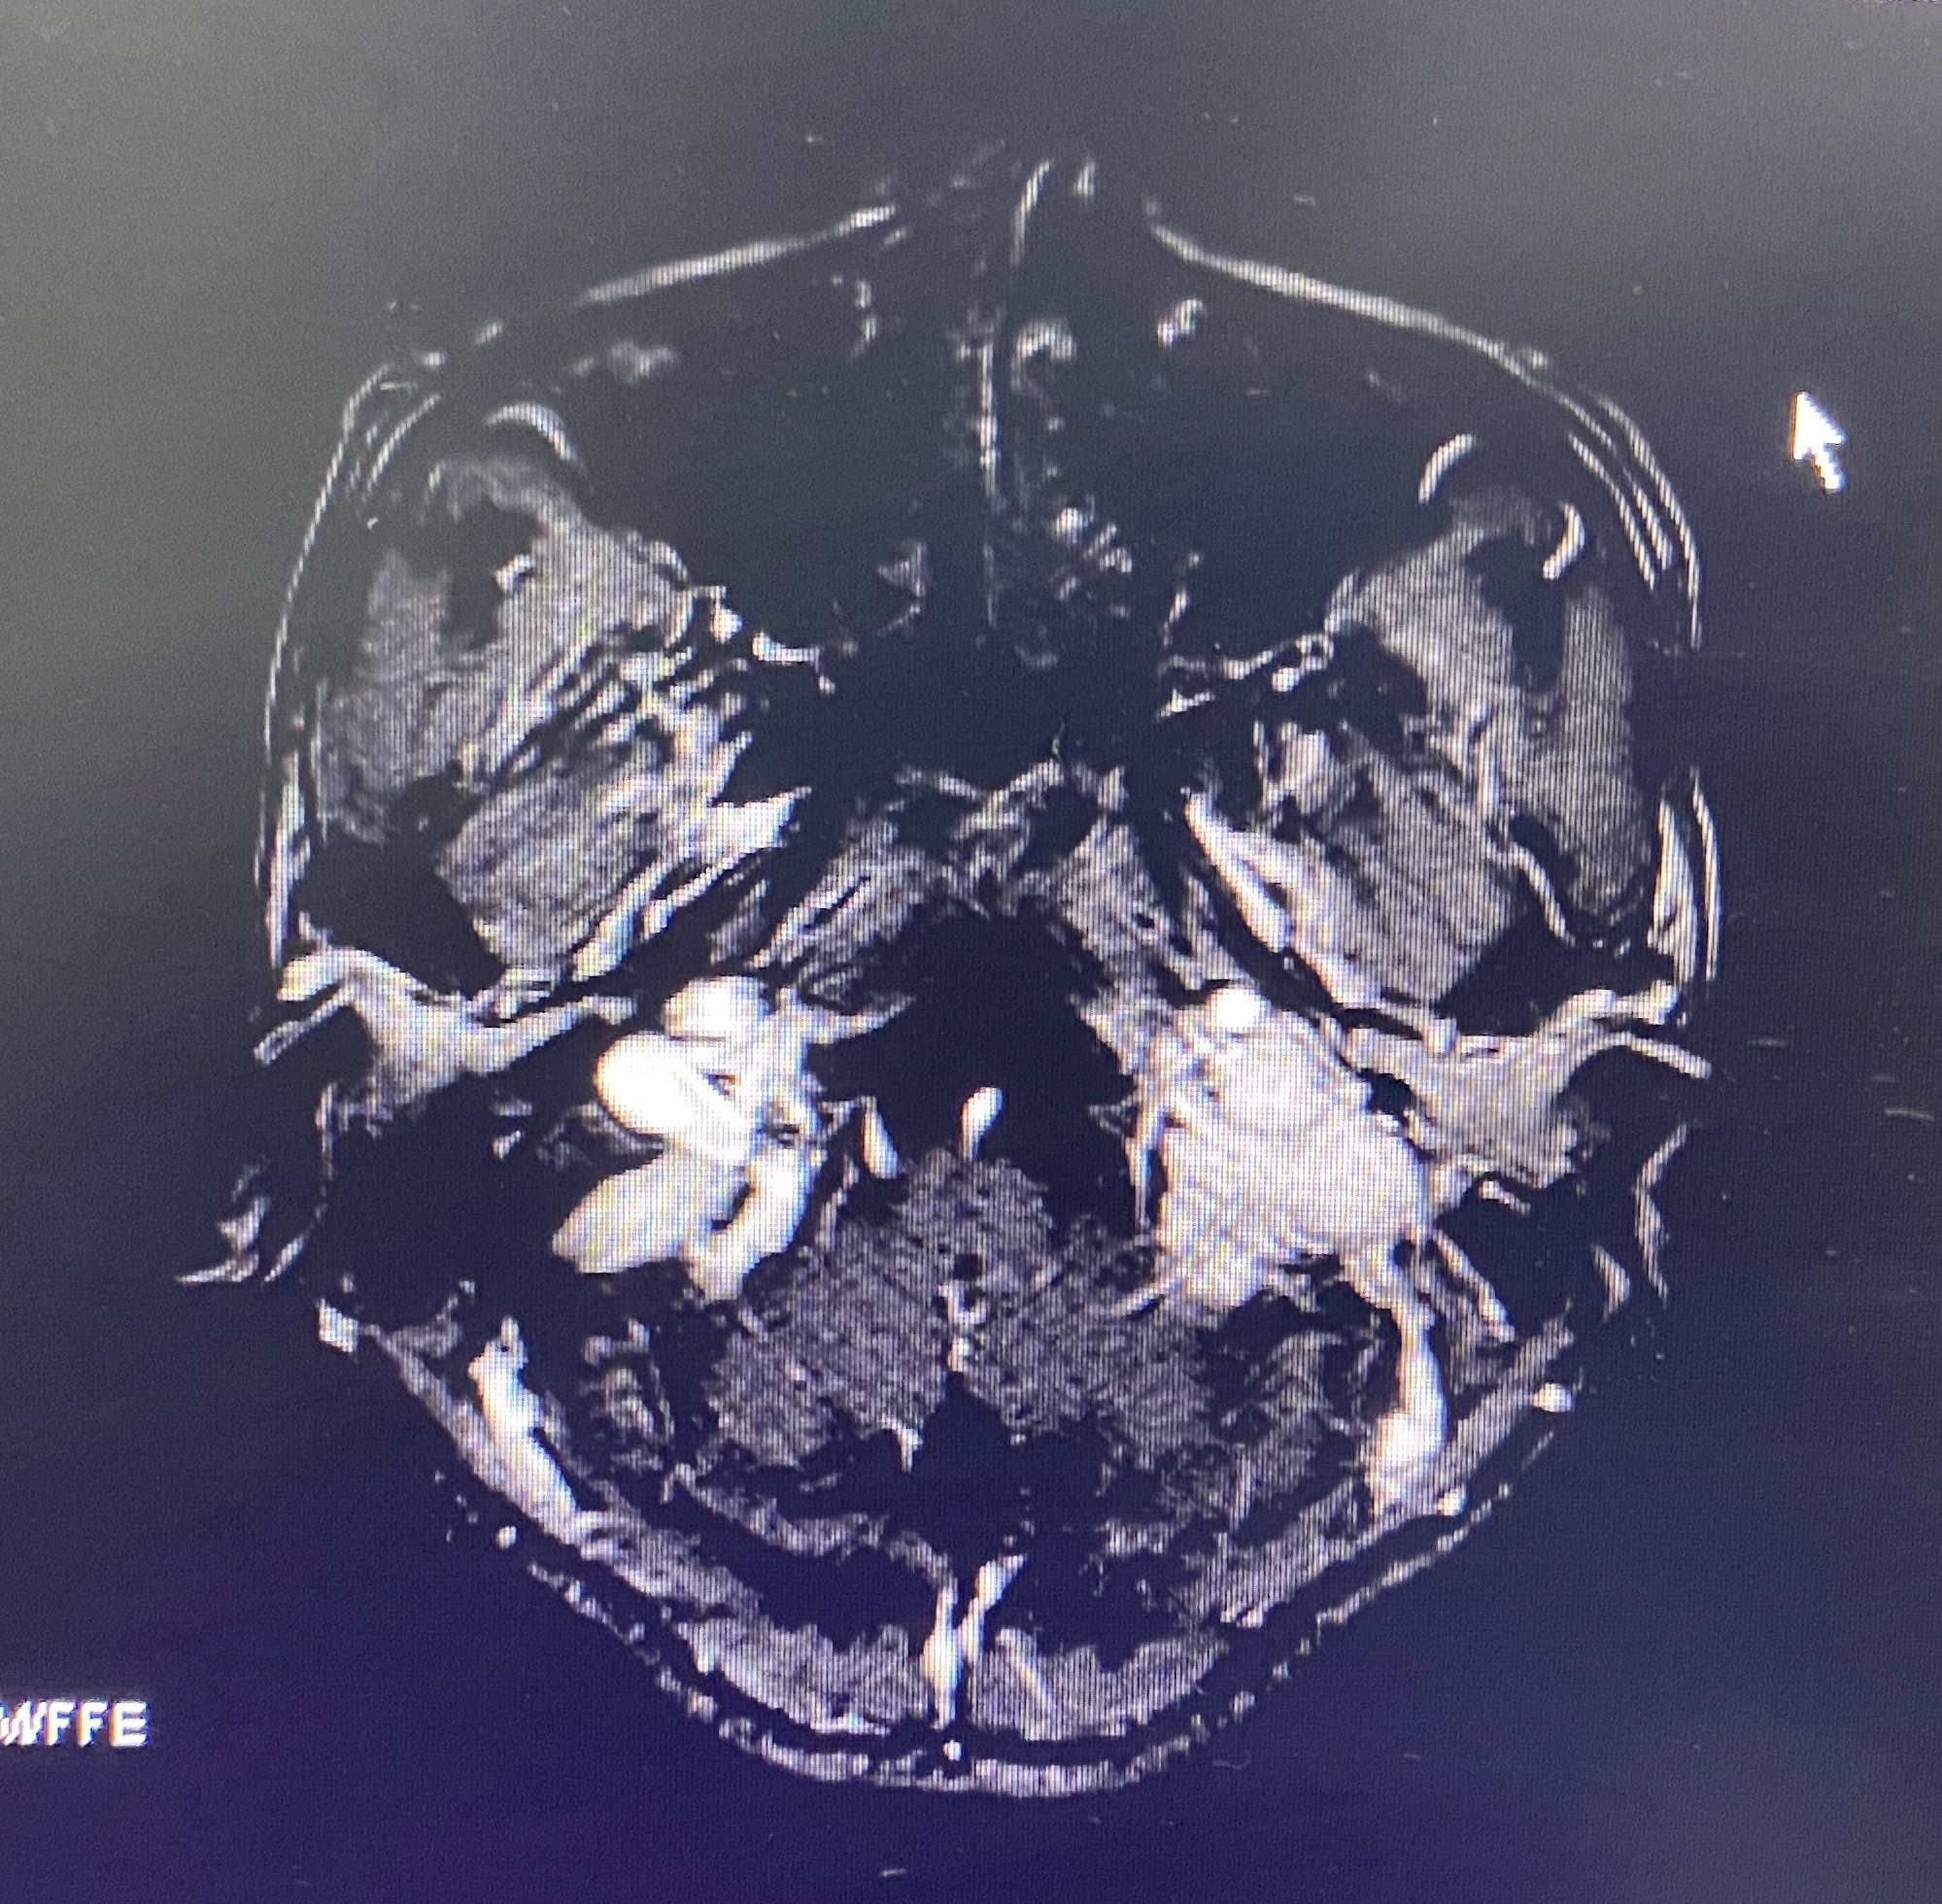

颈静脉孔区肿瘤是神经外科、耳鼻喉科和头颈外科的交界区病变。三国交界常常三不爱管。这个区域的鞘瘤和脑膜瘤可能还相对好做,但血供极其丰富的球瘤却有些麻烦,今天遇到一个中等大小球瘤,术前还是计划用神经外科的视角去处理这个病变,但为了能更好的暴露肿瘤边界以期整块切除控制出血。我们将乳突前方刚出茎乳孔的面神经先暴露出来,以便更快而安全的切除乳突尖。同时在保留半规管和外耳道完整性的前提下向前移位面神经垂直段以达到暴露肿瘤前界的目的,术中切除C-1横突,解除其对前方肿瘤的遮挡(不做椎动脉移位)。